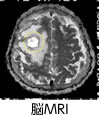

MRI(Magnetic Resonance Imaging systemエムアールアイ)

放射線を使わずに磁気を用いて病巣を写しだします。脳転移などを調べるのに使います。